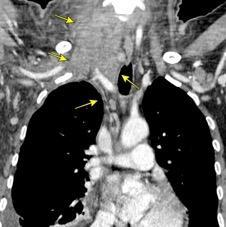

Carcinoma de mama izquierda

American College of Surgeons Oncology Group

Z0011 Trial. Duda sobre la limpieza axilar completa . Humprhey KL et al Do or Not to Do: Axillary Nodal Evaluation after ACOSOG Z011 Tr i a l.. Radiology / Cahoon AR ET AL. Internal Thoracic Lymphadenopathy in Breast Cancer. Radiographics 2017/ Marino MA et al. Lymph Node Imaging in Patients with Primary Breast Cancer:. Concurrent Diagnostic Tools. The Oncologist 2020

Nódulo en língula.

Cirugía de Ca .de mama hace 23 añosedema de brazo y ganglio en axila. ¡Metástasis!.